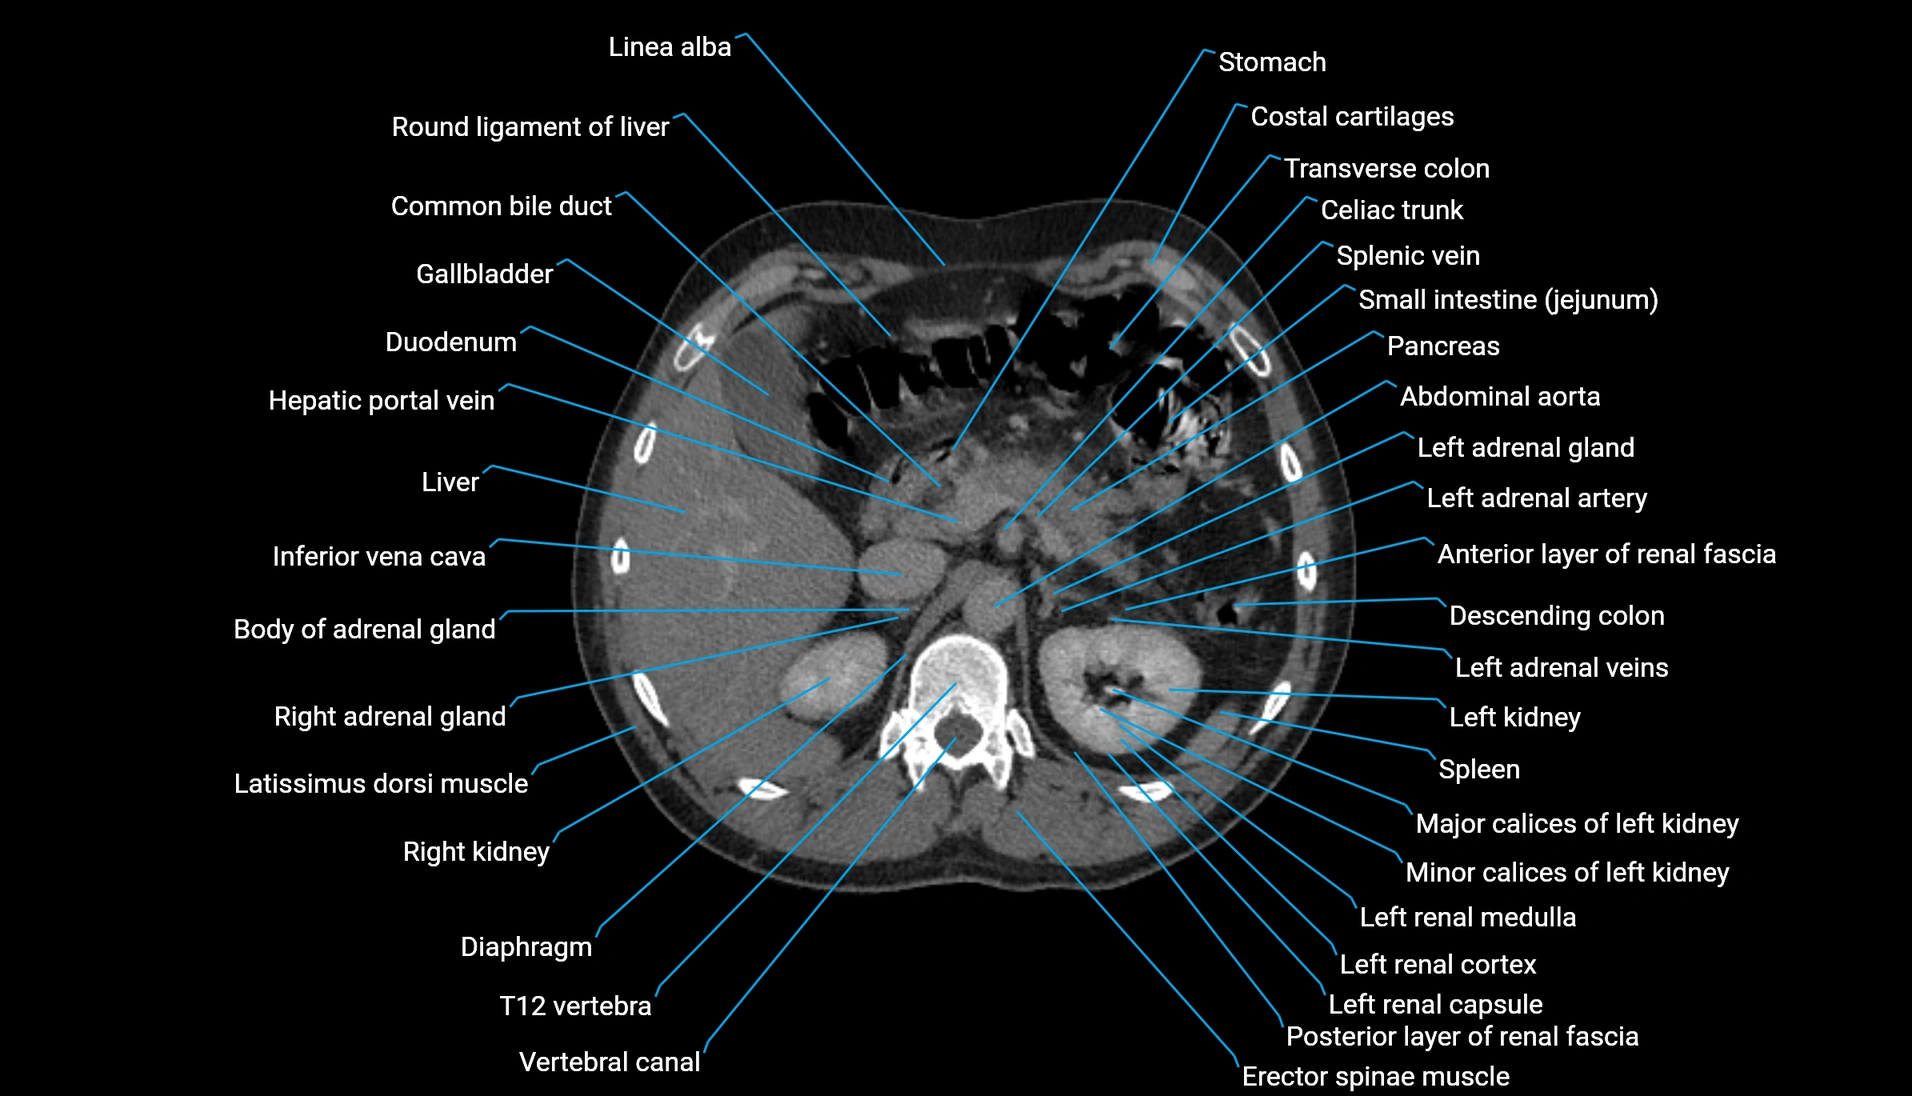

CT Appearance

Non-contrast CT:

-

Demonstrates cortical bone of acetabular rim in excellent detail

Detects fractures, dysplasia, retroversion, or bony overcoverage (pincer impingement)

3D reconstructions used in preoperative hip surgery planning

CT VRT 3D image

CT image